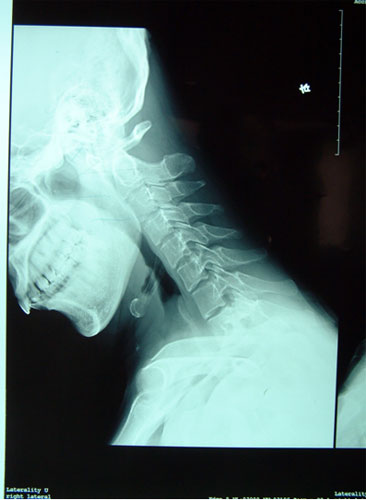

寰枢关节不稳脱位         高位颈脊髓受压迫,瘫痪呼吸困难

融合术后,寰枢关节不稳脱位已经复位